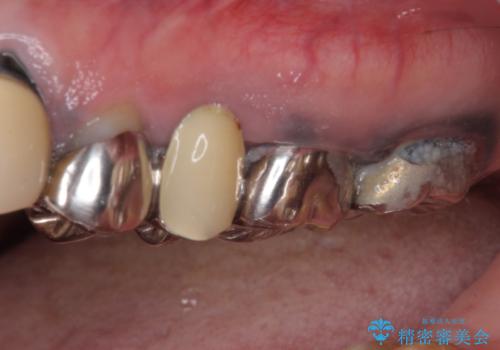

- 全顎的に銀歯が多く、その中でも1番目立って気になる上顎のブリッジをセラミックに替えたいとのことで来院された患者様です。

銀歯の適合が悪く、土台の歯に虫歯多く残っていたので、虫歯除去とファイバーコアによる土台植立を行い、フルジルコニア製ブリッジを装着することとしました。